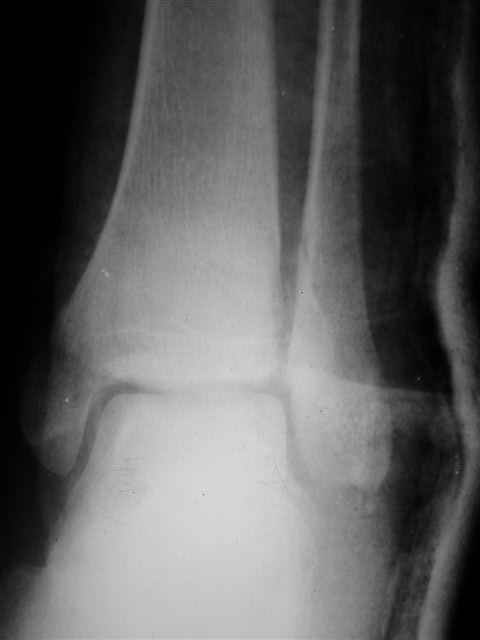

Я предупреждал, что ничего сверхъестественного. Каюсь, что одна из спиц прошла несколько дальше, чем нужно было, но главное - перелом стабилизирован и больной работает суставом в полном объёме, несмотря на представленную раннее травму коленного сустава.

Евгений И Чекашкин